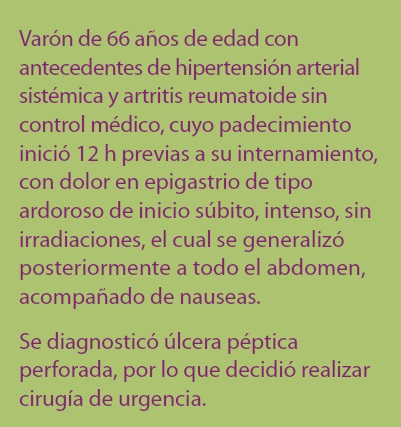

Se trata de paciente varón de 66 años de edad con antecedentes de hipertensión arterial sistémica (HAS) y artritis reumatoide (AR) sin control médico, cuyo padecimiento inició 12 h previas a su internamiento al servicio de urgencias del hospital general "Dr. Gonzalo Castañeda" del Instituto de Seguridad y Servicios Sociales de los Trabajadores del Estado (ISSSTE), con dolor en epigastrio de tipo ardoroso de inicio súbito, intenso, sin irradiaciones, el cual se generalizó posteriormente a todo el abdomen, acompañado de nauseas.

Se diagnosticó úlcera péptica perforada, por lo que decidió realizar cirugía de urgencia.